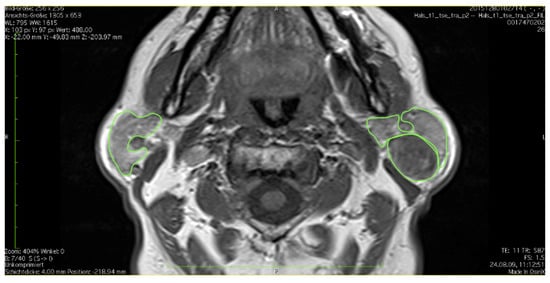

2.2. Standard Operating Procedure